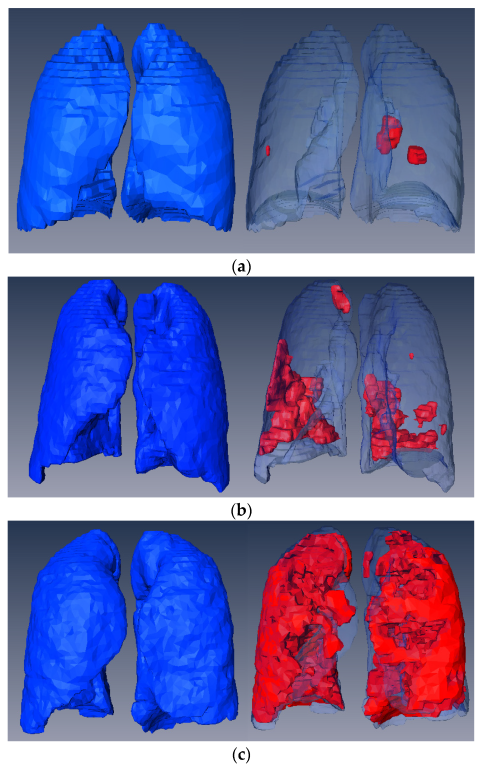

3.7. Volume Reconstruction

| Slices Number | Lungs Volume | Infection Volume | Volume Ratio | Infection Severity | |

|---|---|---|---|---|---|

| P1 | 301 | 3312776 | 408920 | 0.1234 | Moderate |

| P2 | 200 | 4622672 | 181422 | 0.0392 | Mild |

| P3 | 200 | 3498208 | 1015819 | 0.2903 | Severe |

| P4 | 270 | 4536387 | 59529.4 | 0.0131 | Mild |

| P5 | 290 | 4746608 | 80654.7 | 0.0169 | Mild |

| P6 | 213 | 4430680 | 125977 | 0.0284 | Moderate |

| P7 | 249 | 2916567 | 88225.8 | 0.0302 | Moderate |

| P8 | 301 | 3818469 | 278690 | 0.0729 | Moderate |

| P9 | 256 | 2639075 | 101621 | 0.0385 | Moderate |

| P10 | 301 | 2274445 | 396574 | 0.1743 | Severe |

| P11 | 39 | 5516346 | 1067853 | 0.1935 | Severe |

| P12 | 45 | 5736035 | 1044140 | 0.1820 | Severe |

| P13 | 39 | 4617109 | 156231 | 0.0338 | Moderate |

| P14 | 418 | 8186436 | 263209 | 0.0321 | Moderate |

| P15 | 110 | 4138735 | 1023851 | 0.2473 | Severe |

| P16 | 66 | 7882785 | 777185 | 0.0985 | Moderate |

| P17 | 42 | 3136991 | 9.01817 | 0.003 | Mild |

| P18 | 45 | 5729041 | 46320.6 | 0.0080 | Mild |

| P19 | 45 | 6664643 | 148246 | 0.0222 | Mild |

| P20 | 93 | 4842892 | 2844976 | 0.5874 | Severe |